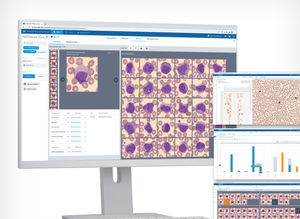

... El software CellaVision Proficiency está diseñado para ayudar a los directores de laboratorio a evaluar, supervisar y promover la competencia del personal en el área de la morfología celular. La herramienta basada en la web facilita la ...